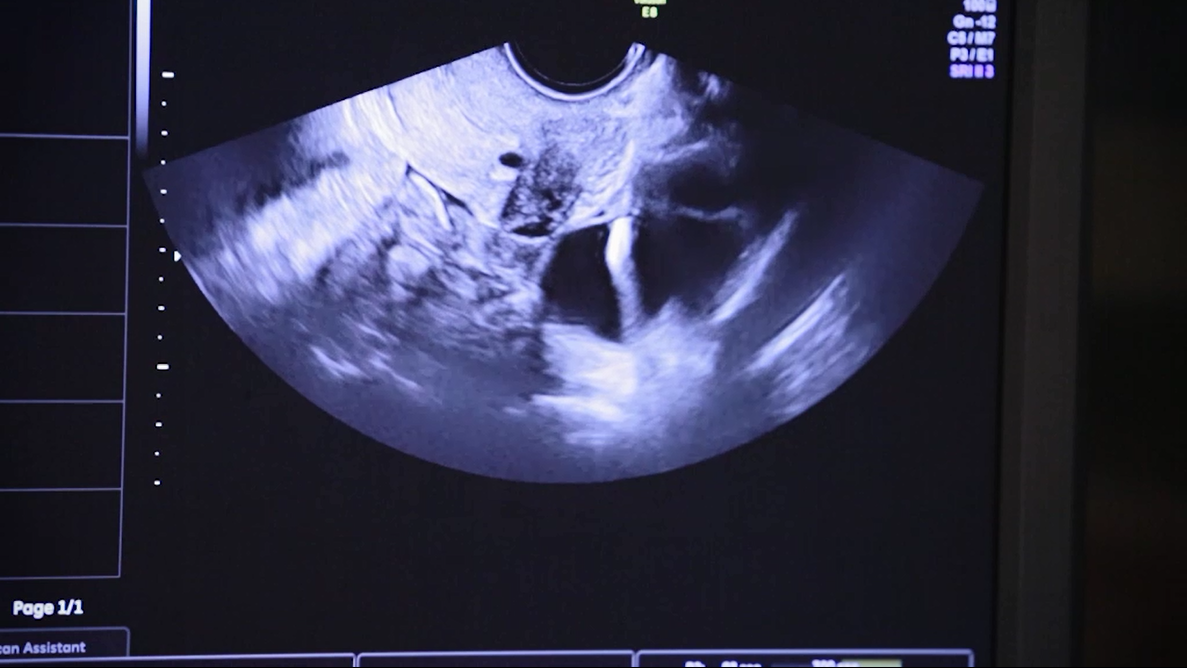

La stimulation peut être débutée à n’importe quelle période du cycle et comporte l’injection sous-cutanée de FSH (hormone folliculostimulante) pendant une dizaine de jours. Un prélèvement d’ovocytes est réalisé par ponction échoguidée, à travers le vagin, sous anesthésie locale ou sédation. Les ovocytes ponctionnés sont soit congelés (vitrification), soit fécondés par fécondation in vitro (FIV). Les ovocytes ou embryons sont congelés et peuvent être cryoconservés plusieurs années sans altération de leur potentiel. Le nombre d’ovocytes et d’embryons reste limité après une seule tentative.

Un prélèvement d’ovocytes immatures (sans stimulation hormonale) est réalisé par ponction échoguidée, à travers le vagin, sous anesthésie locale ou sédation. Les ovocytes sont mis en culture pendant 24 à 48 heures afin de les faire maturer (maturation in vitro des ovocytes, MIV). La moitié environ des ovocytes atteindront le stade mature et seront soit congelés (vitrification), soit fécondés au laboratoire (fécondation in vitro, FIV). Les limites de la technique tiennent au nombre aléatoire d’ovocytes immatures recueillis et la qualité des ovocytes et embryons cryopréservés moins bonne qu’après stimulation ovarienne.